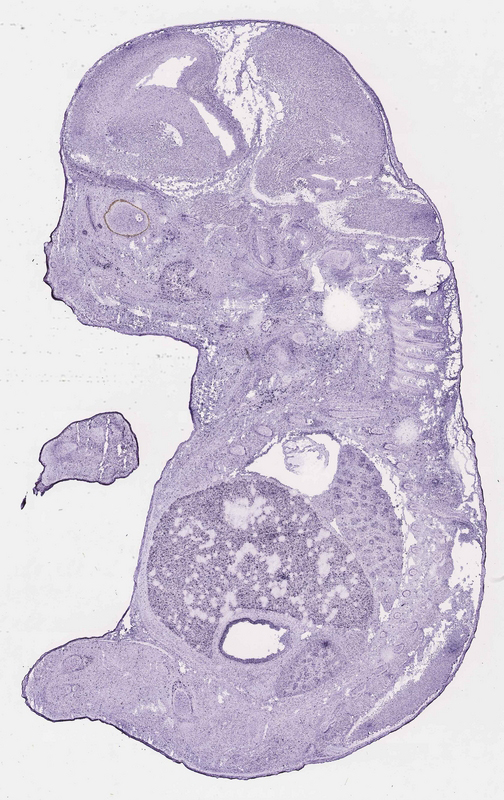

Reference: J:153498 Diez-Roux G, et al., A high-resolution anatomical atlas of the transcriptome in the mouse embryo. PLoS Biol. 2011;9(1):e1000582

Gene symbol: Slc9a1

Gene name: solute carrier family 9 (sodium/hydrogen exchanger), member 1

Specimen euxassay_001642_02: embryonic day 14.5 (more )

TS23: stomach Moderate Regionally restricted euxassay_001642_02